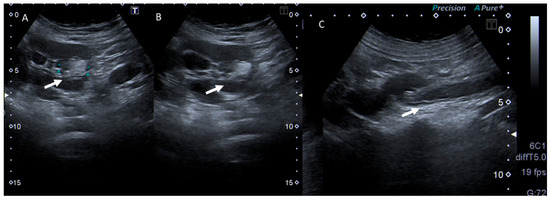

4. Clinical Setting: Abdominal Pain

6. Biliary Tract and Pancreatic Diseases

7. Ureterolithiasis